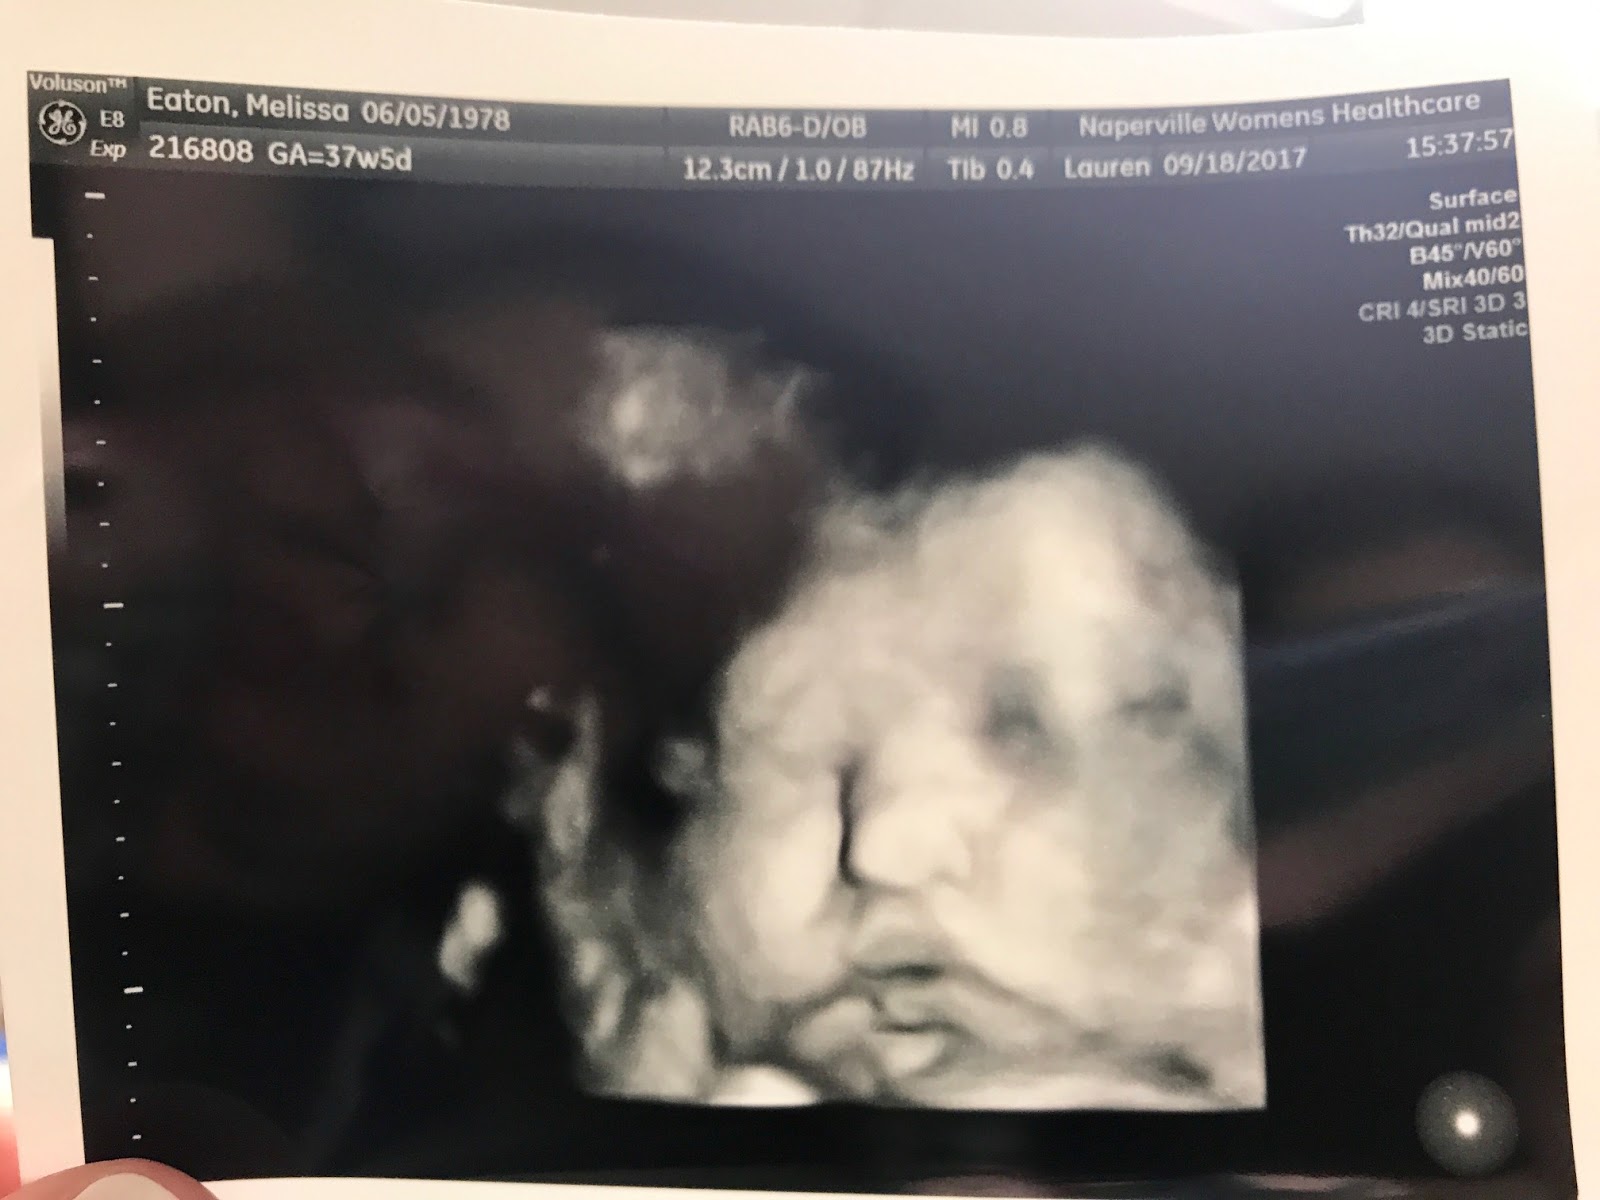

This is a 3D ultrasound of her face. They checked all of her organs today and everything looks normal. That's her little hand up by her face, just like the

last ultrasound.